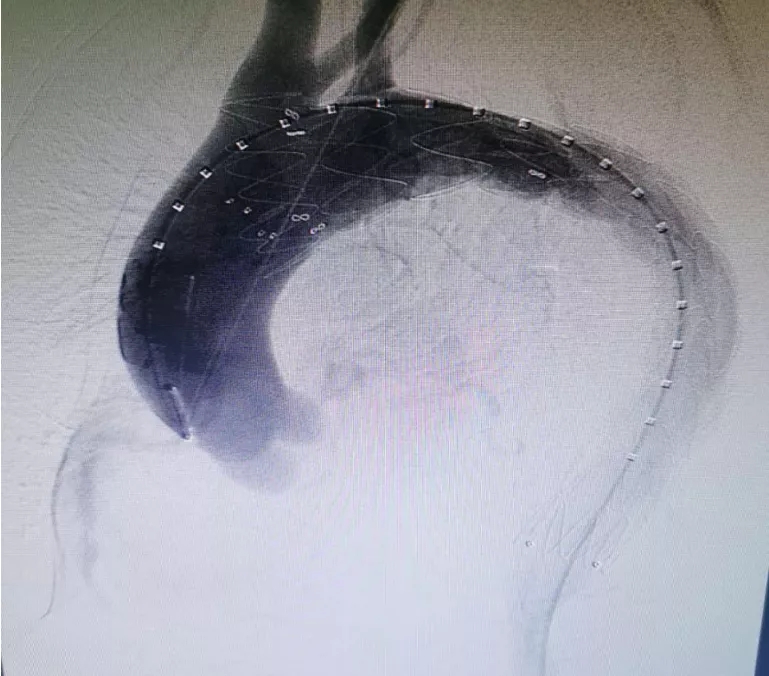

术前患者CTA检查

术中见主动脉夹层(stanford B型),破口位于降主动脉起始处,破口大小1厘米,假腔压迫真腔特别明显,造成真腔狭窄。

定位释放支架,精准定位、精确制导,效果立竿见影,无缝连接,假腔完全消失,无内漏,血流通畅(见下图)。